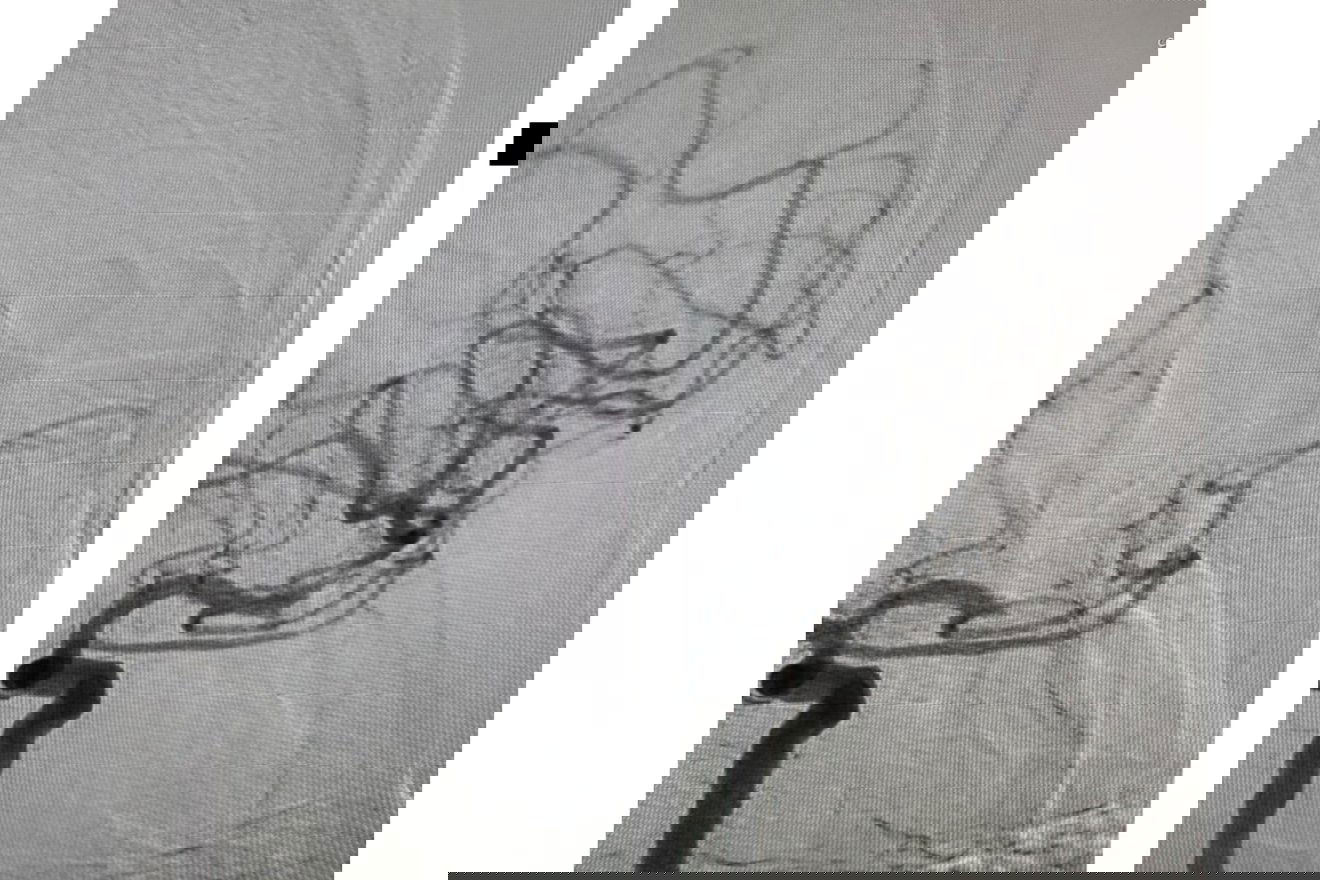

Fotó: Csíkszeredai Megyei Sürgősségi Kórház